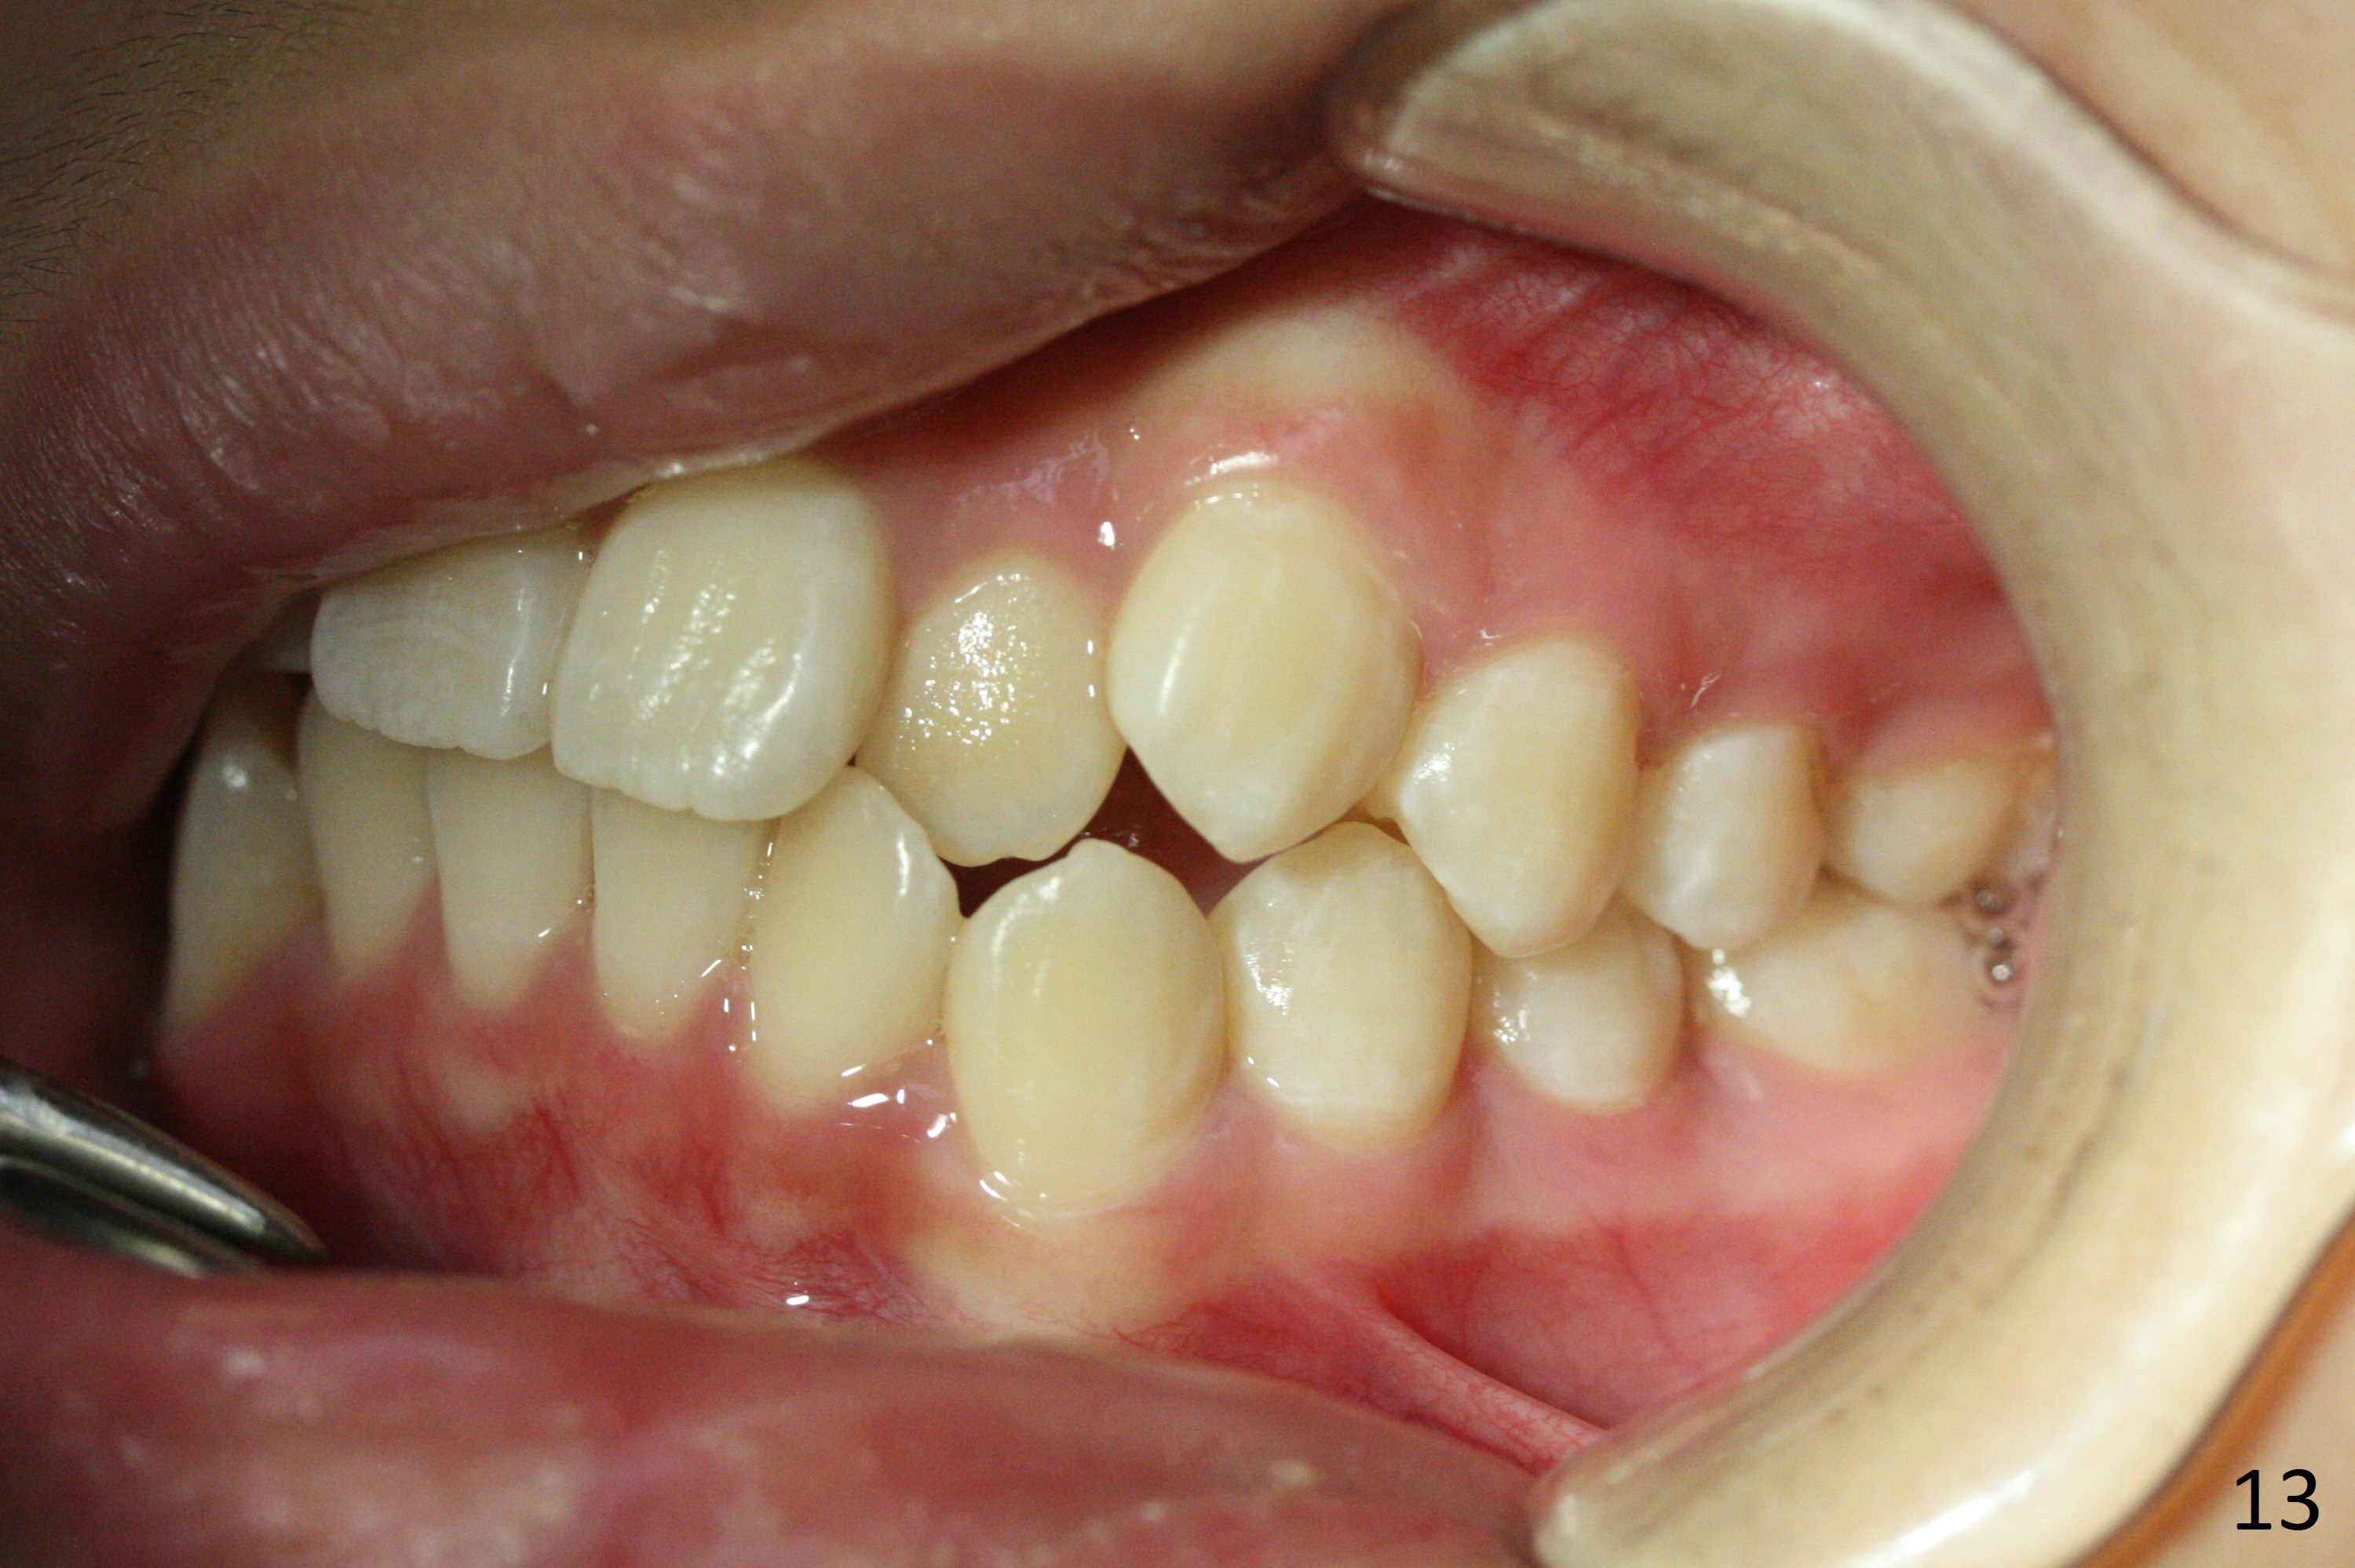

Shallow Overbite

A 12-year-old man has mild lip protrusion (Fig.1,6,7). Orthodontics will be conducted without extraction. Unlike his elder brother, the overbite is shallow. With anterior bracket differential (4-4-5 mm) and mild bimaxillary protrusion, open bite will be created? Or 4-4-4.5mm scheme should be adopted to avoid open bite?